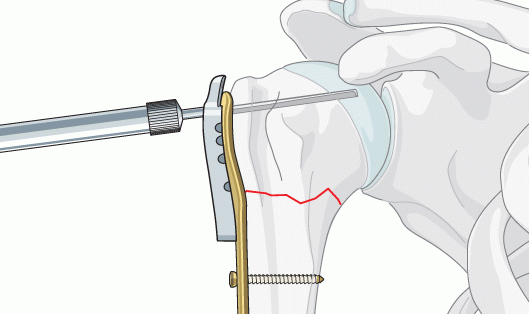

医疗骨钻骨锯无刷电机及驱动器设计

目前国内骨钻骨锯主流的电机还是有刷,在使用的过程中有刷电机的性能逐渐不能满足更精细的手术要求,国外一线的骨钻骨锯品牌已经将产品升级换代成无刷电机加驱动器的新一代医疗产品。在使用的过程中有更高的工作效率,更好的工作效果。

但是国内无刷电机和驱动器的研发和设计是长期以来的短板,特别是面对这种比较严苛的使用环境,还要符合医疗认证,同时高温消毒的条件下也要保证产品的稳定性。这就无形中加大了该产品的研发设计难度,也导致了客户长期以来找不到好的电机和驱动器来满足他们新产品的需求。